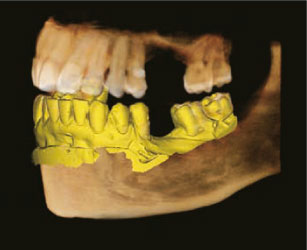

Анатомическое поле сканирования

Инновационное поле обзора компьютерном томографе Green Smart обеспечивает захват объема в форме зубной дуги, что обеспечивает попадание более широкой зоны интереса по сравнению с другими аппаратами с аналогичными по размеру полями обзора. Обычно, поле обзора 10x8,5 достаточно для визуализации 8-х зубов. В случае ретенированных 3-х моляров высока вероятность того, что корни зуба могут быть срезаны. "Арочный объем" исключает такую вероятность, демонстрируя скрытую область зубного ряда.